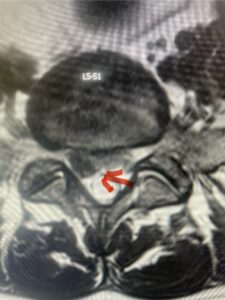

In this next case, this patient is a 47 year-old female who presents with intractable low back pain with severe pain, numbness, and weakness in the right lower extremity that had gotten progressively worse over a year. The patient had failed conservative management including physical therapy and epidurals. She was noted to have ⅘ weakness of plantar flexion. MRI demonstrated a large right L5-S1 disc herniation with severe compression of the descending right S1 nerve root (Fig 3). It was decided to perform a right L5-S1 hemilaminectomy for removal of the disc fragment and decompress the S1 nerve root. When you expose the disc, one must be certain to release any anterior adhesions to the nerve root in order to prevent a dural tear during retraction of the nerve root. It is also important to make sure during exposure and you finally encounter the dura after removing the ligamentum and fat, to make sure you are looking at the nerve root and not the main trunk of the thecal sac because if you don’t you can avulse or damage the nerve root if you retract the wrong structure.

Fig. 3a: Sagittal and axial T2-weighted lumbar MRI images demonstrating large right L5-S1 disc herniation (red arrows)